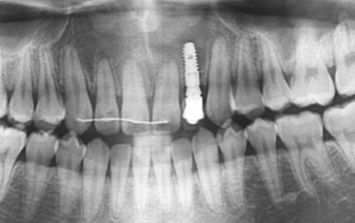

왼쪽 어금니 상실로 내원한 환자분. 위 턱뼈의 경우 아래턱뼈보다 얇고 상악동 있어 임플란트를 실패할 가능성이 높습니다.

턱뼈의 해부학적 구조를 충분히 고려한 상악동 뼈이식 후 임플란트를 식립하였습니다.